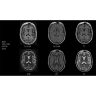

Благодаря революционному программному пакету Silent Suite уровень шума снижается до 77 дБ, что всего на 3 дБ выше уровня окружающей среды. Программный пакет Silent Suite теперь включает полный пакет приложений для исследования ЦНС (T1, T2 FLAIR, DWI10, МРА). Кроме того, мы расширили возможности визуализации Silent за пределы ЦНС для исследований скелетно-мышечной системы и позвоночника. Silent Suite – платформа, содержащая в себе все импульсные последовательности для бесшумного сканирования.